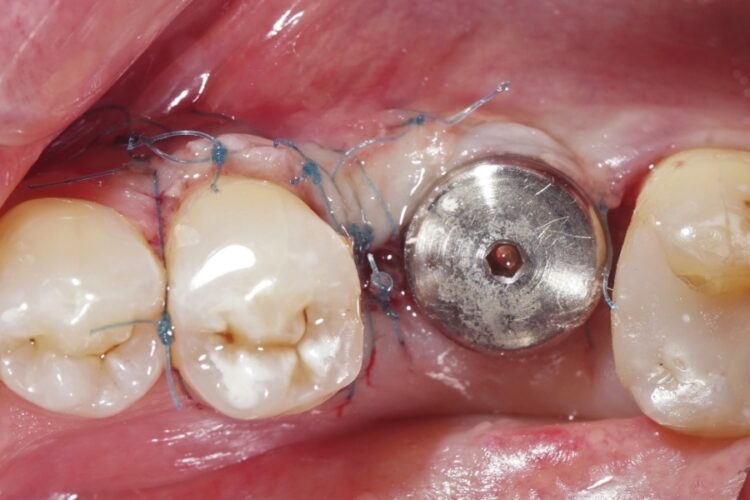

Клинический кейс имплантации

Все этапы: от компьютерной томограммы до установки коронки на имплант.

Установленный имплант: 4.5 мм на 11.5 мм

Коронка на имплант: дисиликат лития, винтовая фиксация, изготовлена в клинике за 3 часа.

Абатмент: индивидуальный титановый.

Длительность имплантации: 1.5 часа.

Промежуток от импланта до коронки: 3 месяца.

Заключение: проведена установка импланта с одновременной пластикой десны и формированием межзубных сосочков. В имплант установлен формирователь десны. Рана ушита. Швы необходимо снять через 10-14 дней. Даны рекомендации в послеоперационный период.

Установка коронки на имплант запланирована через 3 месяца.